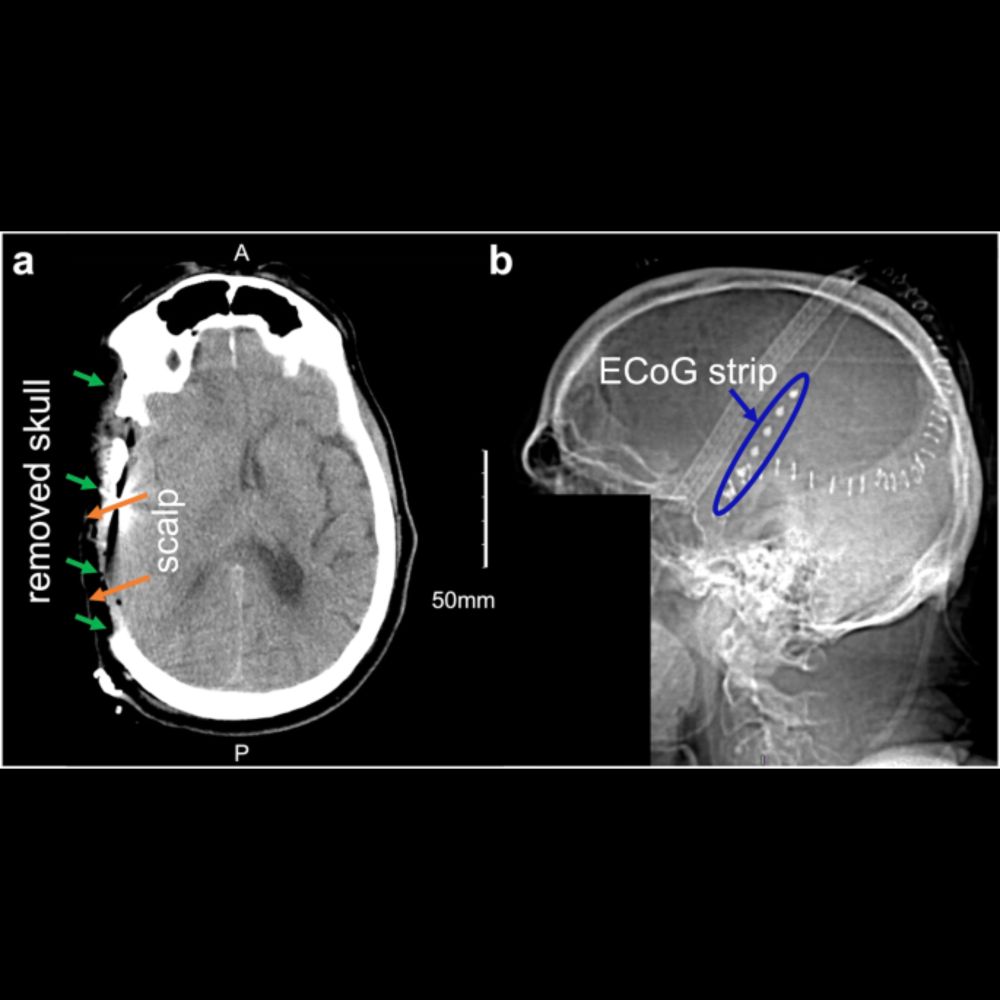

A lab developing and highlighting neurotechnologies and biotechnologies that work for all. Focus on developing novel engineering and computational tools and theory, and translating them into the clinic. PI Pulkit Grover, PhD.